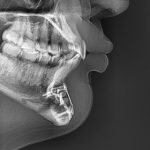

Combined Infraorbital–Malar–Maxillary Reconstruction (The Custom “Midface Mask” Implant)

Combined infraorbital–malar–maxillary augmentation represents a comprehensive skeletal reconstruction of the central and lateral midface. Commonly referred to as a custom midface mask implant, this technique restores deficient projection across the infraorbital rim, anterior maxilla, paranasal region, and zygomatic body in a single, continuous construct. Unlike isolated infraorbital or malar implants, or even combined infraorbital-malar implant, Read More…